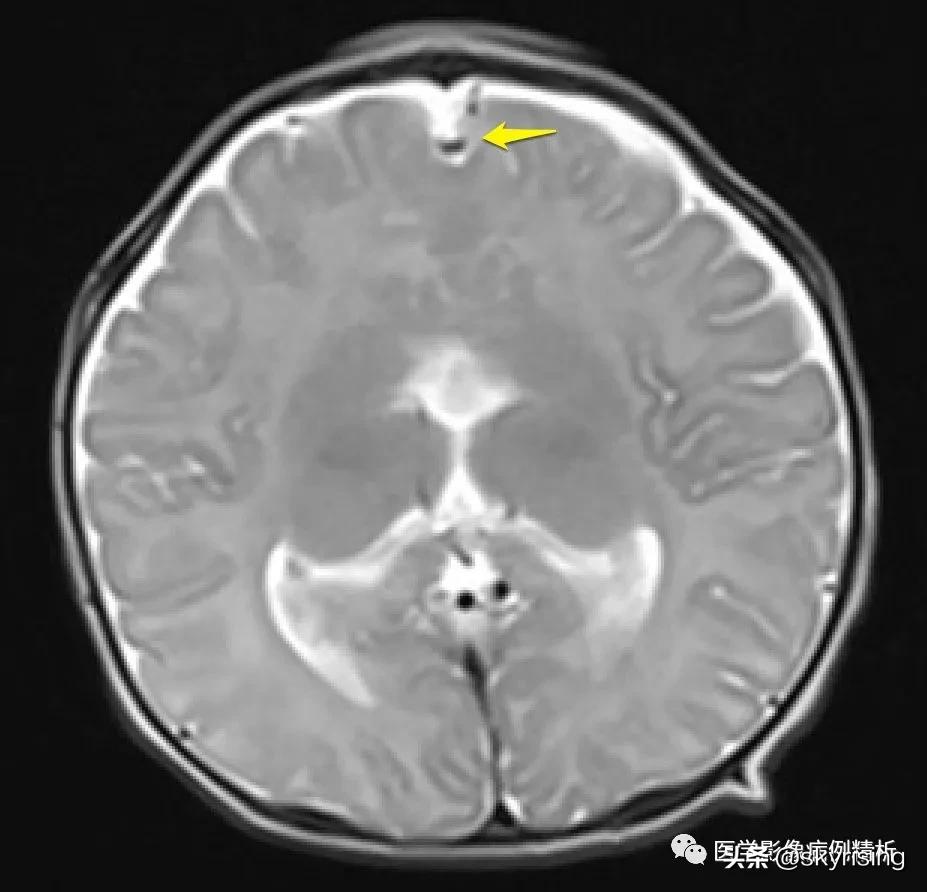

T1WI轴位像:黄色箭头所示可见大脑前纵裂缺如,双侧额叶脑实质融合,胼胝体膝部未见显示。透明隔缺如,双侧侧脑室融合呈蝙蝠翼样改变。侧脑室额角未见显示,体部平行于矢状线,后角失去张力、变尖。

黄色箭头所示为大脑前动脉单支血管影,被推移至融合脑实质前。枕角形态尚可。双侧额部蛛网膜下腔增宽,见细带状液体信号,提示硬膜下积液。

红色箭头所示为融合额叶脑实质,大脑纵裂不完全。白色箭头所示为双侧视神经,形态对称、大小、信号未见异常,提示视神经发育正常。